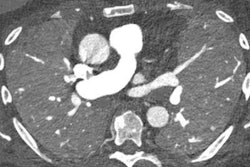

![Meningioma in a 90-year-old man. Axial [photon-counting] CT image acquired at 120 kV (A) VM image at 45 keV (B), and EID CT image (C) show improved visualization of the dural tail (arrow in A and B) compared with that in C (arrow in C). Image and caption courtesy of RadioGraphics.](https://img.auntminnie.com/files/base/smg/all/image/2023/04/am.2023_04_10_22_07_2198_2023_04_11_pcct_image.png?auto=format%2Ccompress&fit=max&q=70&w=400) Meningioma in a 90-year-old man. Axial [photon-counting] CT image acquired at 120 kV (A) VM image at 45 keV (B), and EID CT image (C) show improved visualization of the dural tail (arrow in A and B) compared with that in C (arrow in C). Image and caption courtesy of RadioGraphics.

Meningioma in a 90-year-old man. Axial [photon-counting] CT image acquired at 120 kV (A) VM image at 45 keV (B), and EID CT image (C) show improved visualization of the dural tail (arrow in A and B) compared with that in C (arrow in C). Image and caption courtesy of RadioGraphics.The technique shows promise particularly for imaging small structures such as fine cortical and trabecular detail in musculoskeletal imaging, small bronchi of the lungs, the temporal bone and carotid artery in the brain, and vascular branches of the heart (coronary arteries and runoff vessels in the forearm, wrist, hand, leg, and foot).